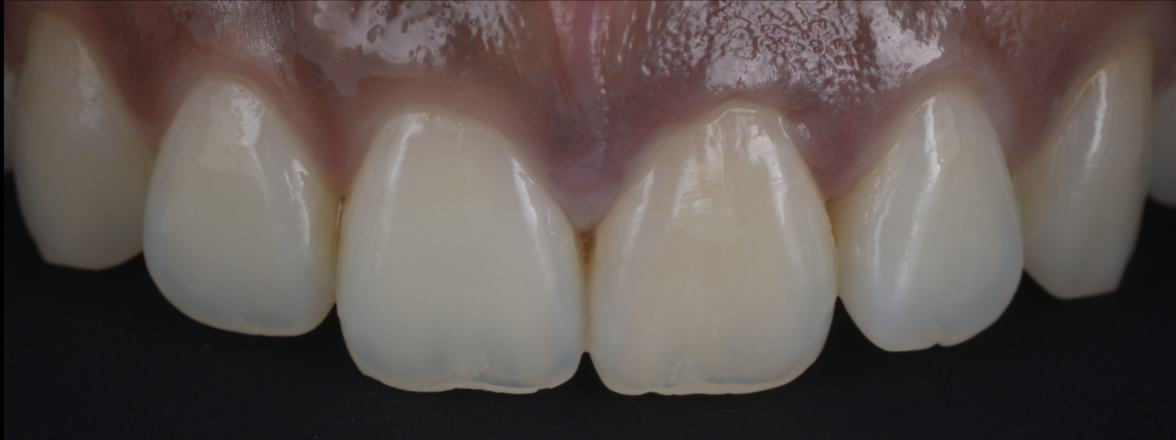

治療前

治療後

| 治療内容 | ラバーダム、マイクロスコープ、 MTAを用いた精密根管治療 歯根端切除術 |